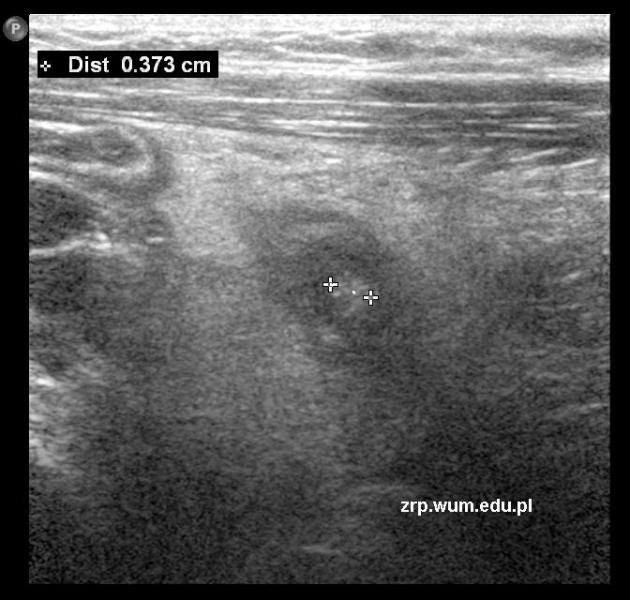

Rozpoznanie: W badaniu USG - W prawym dole biodrowym widoczny zmieniony zapalnie wyrostek robaczkowy, pogrubiały do 11mm, z kamieniem kałowym śr. ok. 4mm; tkanka tłuszczowa w otoczeniu pogrubiała, hyperechogeniczna.